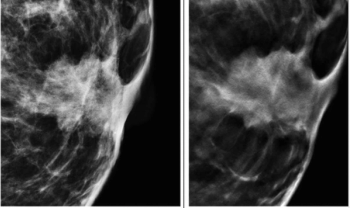

Emerging research suggests that combining full-field digital mammography and whole-breast ultrasound tomography provides superior sensitivity in detecting BI-RADS 4 lesions and superior specificity in diagnosing BI-RADS 3 lesions than mammography alone in women with dense breasts.

In a study of asymptomatic women at elevated risk for breast cancer, digital breast tomosynthesis (DBT) demonstrated equivalent sensitivity to full-field digital mammography (FFDM) for three out of four reviewing radiologists and detected no additional cancers beyond those detected with FFDM.

Offering comparable sensitivity to radiologists for detecting contralateral breast cancer on mammography images, an emerging adjunctive AI software may also facilitate earlier diagnosis, according to study findings presented at the at the 2024 American Society of Clinical Oncology (ASCO) Annual Meeting.

In a retrospective study involving nearly 119,000 women, researchers found that implementation of AI into mammography screening increased the positive predictive value by 11 percent, increased small cancer detection by 8.3 percent and reduced reading workload by approximately 33 percent.